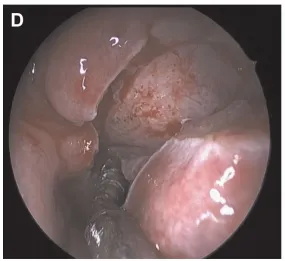

▼由下向上、由后向前切开右侧下鼻腔粘膜斜向切开(图C和D)。

▼使用3mm高速弯曲金刚石钻头磨除下鼻甲(Midas Rex LegendR telescope,Medtronic,Dublin,Ireland)。在SS下方的上斜坡钻孔磨除骨质以暴露肿瘤(图E)。